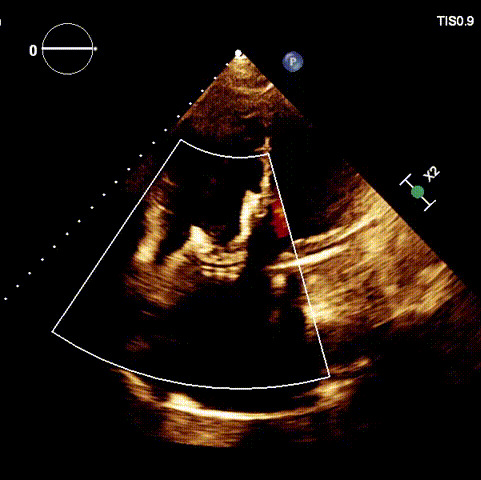

術(shù)后超聲

近日,廈門大學(xué)心血管病醫(yī)院王焱教授帶領(lǐng)的結(jié)構(gòu)性心臟病團(tuán)隊,成功應(yīng)用LuX-Valve Plus經(jīng)血管三尖瓣置換系統(tǒng),為一例高危三尖瓣重度反流患者開展經(jīng)血管三尖瓣置換手術(shù)。此次手術(shù)系LuX-Valve Plus人工瓣膜在福建省的首例植入,手術(shù)過程順利,術(shù)后患者三尖瓣反流顯著改善,標(biāo)志著由葛均波院士團(tuán)隊作為主要研究者的LuX-Valve Plus經(jīng)血管三尖瓣置換系統(tǒng)全國多中心臨床研究的再一次成功實踐,為三尖瓣介入治療的醫(yī)學(xué)循證打下了夯實的基礎(chǔ)。 、

手術(shù)在全麻狀態(tài)下開展,海軍軍醫(yī)大學(xué)附屬長海醫(yī)院陸方林教授與廈門心血管病醫(yī)院王焱院長共同上臺,為患者進(jìn)行手術(shù)。此次手術(shù)采用經(jīng)右側(cè)頸靜脈入路的方式將輸送器送入患者心臟內(nèi),在TEE及DSA引導(dǎo)下調(diào)整輸送器頭端角度,使得輸送器與三尖瓣瓣環(huán)平面垂直。在輸送器進(jìn)入右心室后釋放室間隔錨定裝置,而后釋放瓣葉夾持件(2個耳片結(jié)構(gòu))成垂直狀態(tài)。在TEE及DSA確定夾持件固定至三尖瓣葉根部且位于右室側(cè)后釋放人工瓣心房側(cè)盤片。隨后調(diào)整瓣膜同軸性以及室間隔錨定件位置(貼合室間隔),前推藏針管并固定,進(jìn)而釋放室間隔錨定裝置,并再次確認(rèn)瓣膜位置、穩(wěn)定性及同軸性,合攏輸送鞘后撤出輸送器,完成LuX-Valve Plus人工三尖瓣瓣膜的植入。